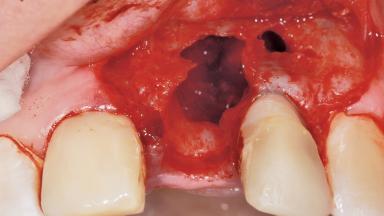

Late Placement of an Implant in a Maxillary Left Central Incisor Site

A 36-year-old female patient was referred for the replacement of the upper left central incisor (tooth 21), which had fractured. Although the tooth had been asymptomatic for many years, the crown began to loosen, at which time she presented to her dentist for an assessment. Teeth 21 and 22 had both been endodontically treated many years previously. She was a healthy individual and a non-smoker.

Bone Augmentation Horizontal|Staged

Augmentation Materials Xenogenous|Membrane

Soft Tissue Anatomy Intact Defective

Bone Volume Horizontally and vertically sufficient Horizontally deficient Deficient vertically or deficient vertically AND horizontally

Bone Volume Deficient horizontally, requiring prior grafting